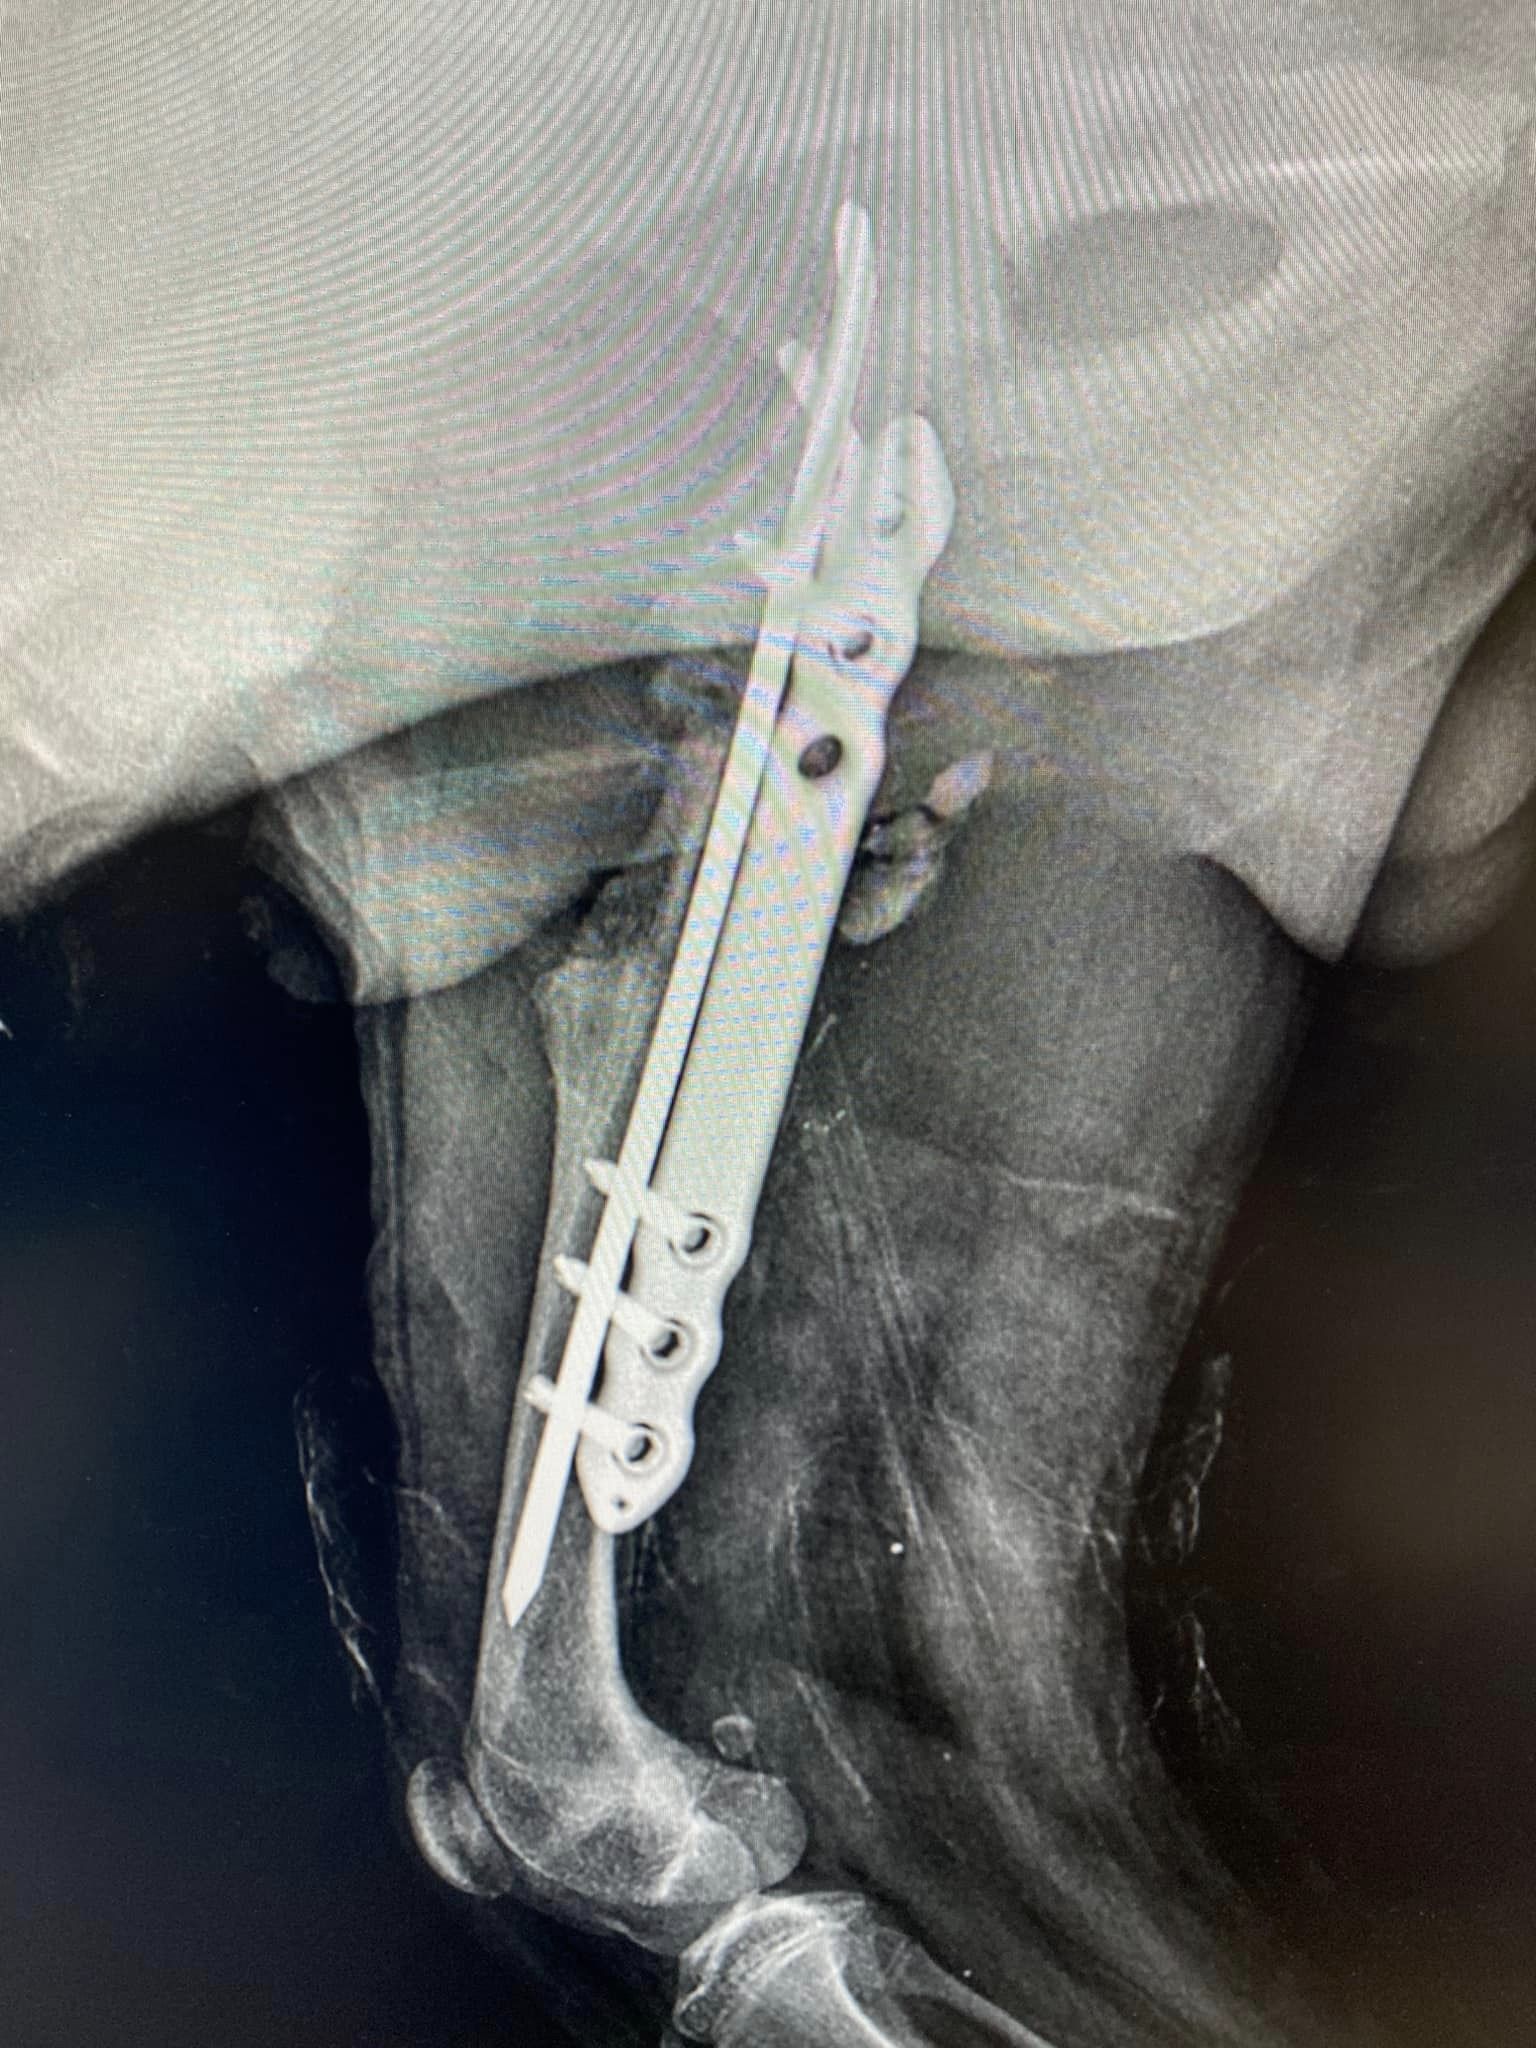

Zastosowanie płyty mostującej 1 lutego 202318 grudnia 2023 Zastosowanie naszej płytki mostującej, cieszy bardzo! Pozdrawiamy specjalistów z Przychodnia weterynaryjna „Kiełbowicz” ! Śledź nas na: